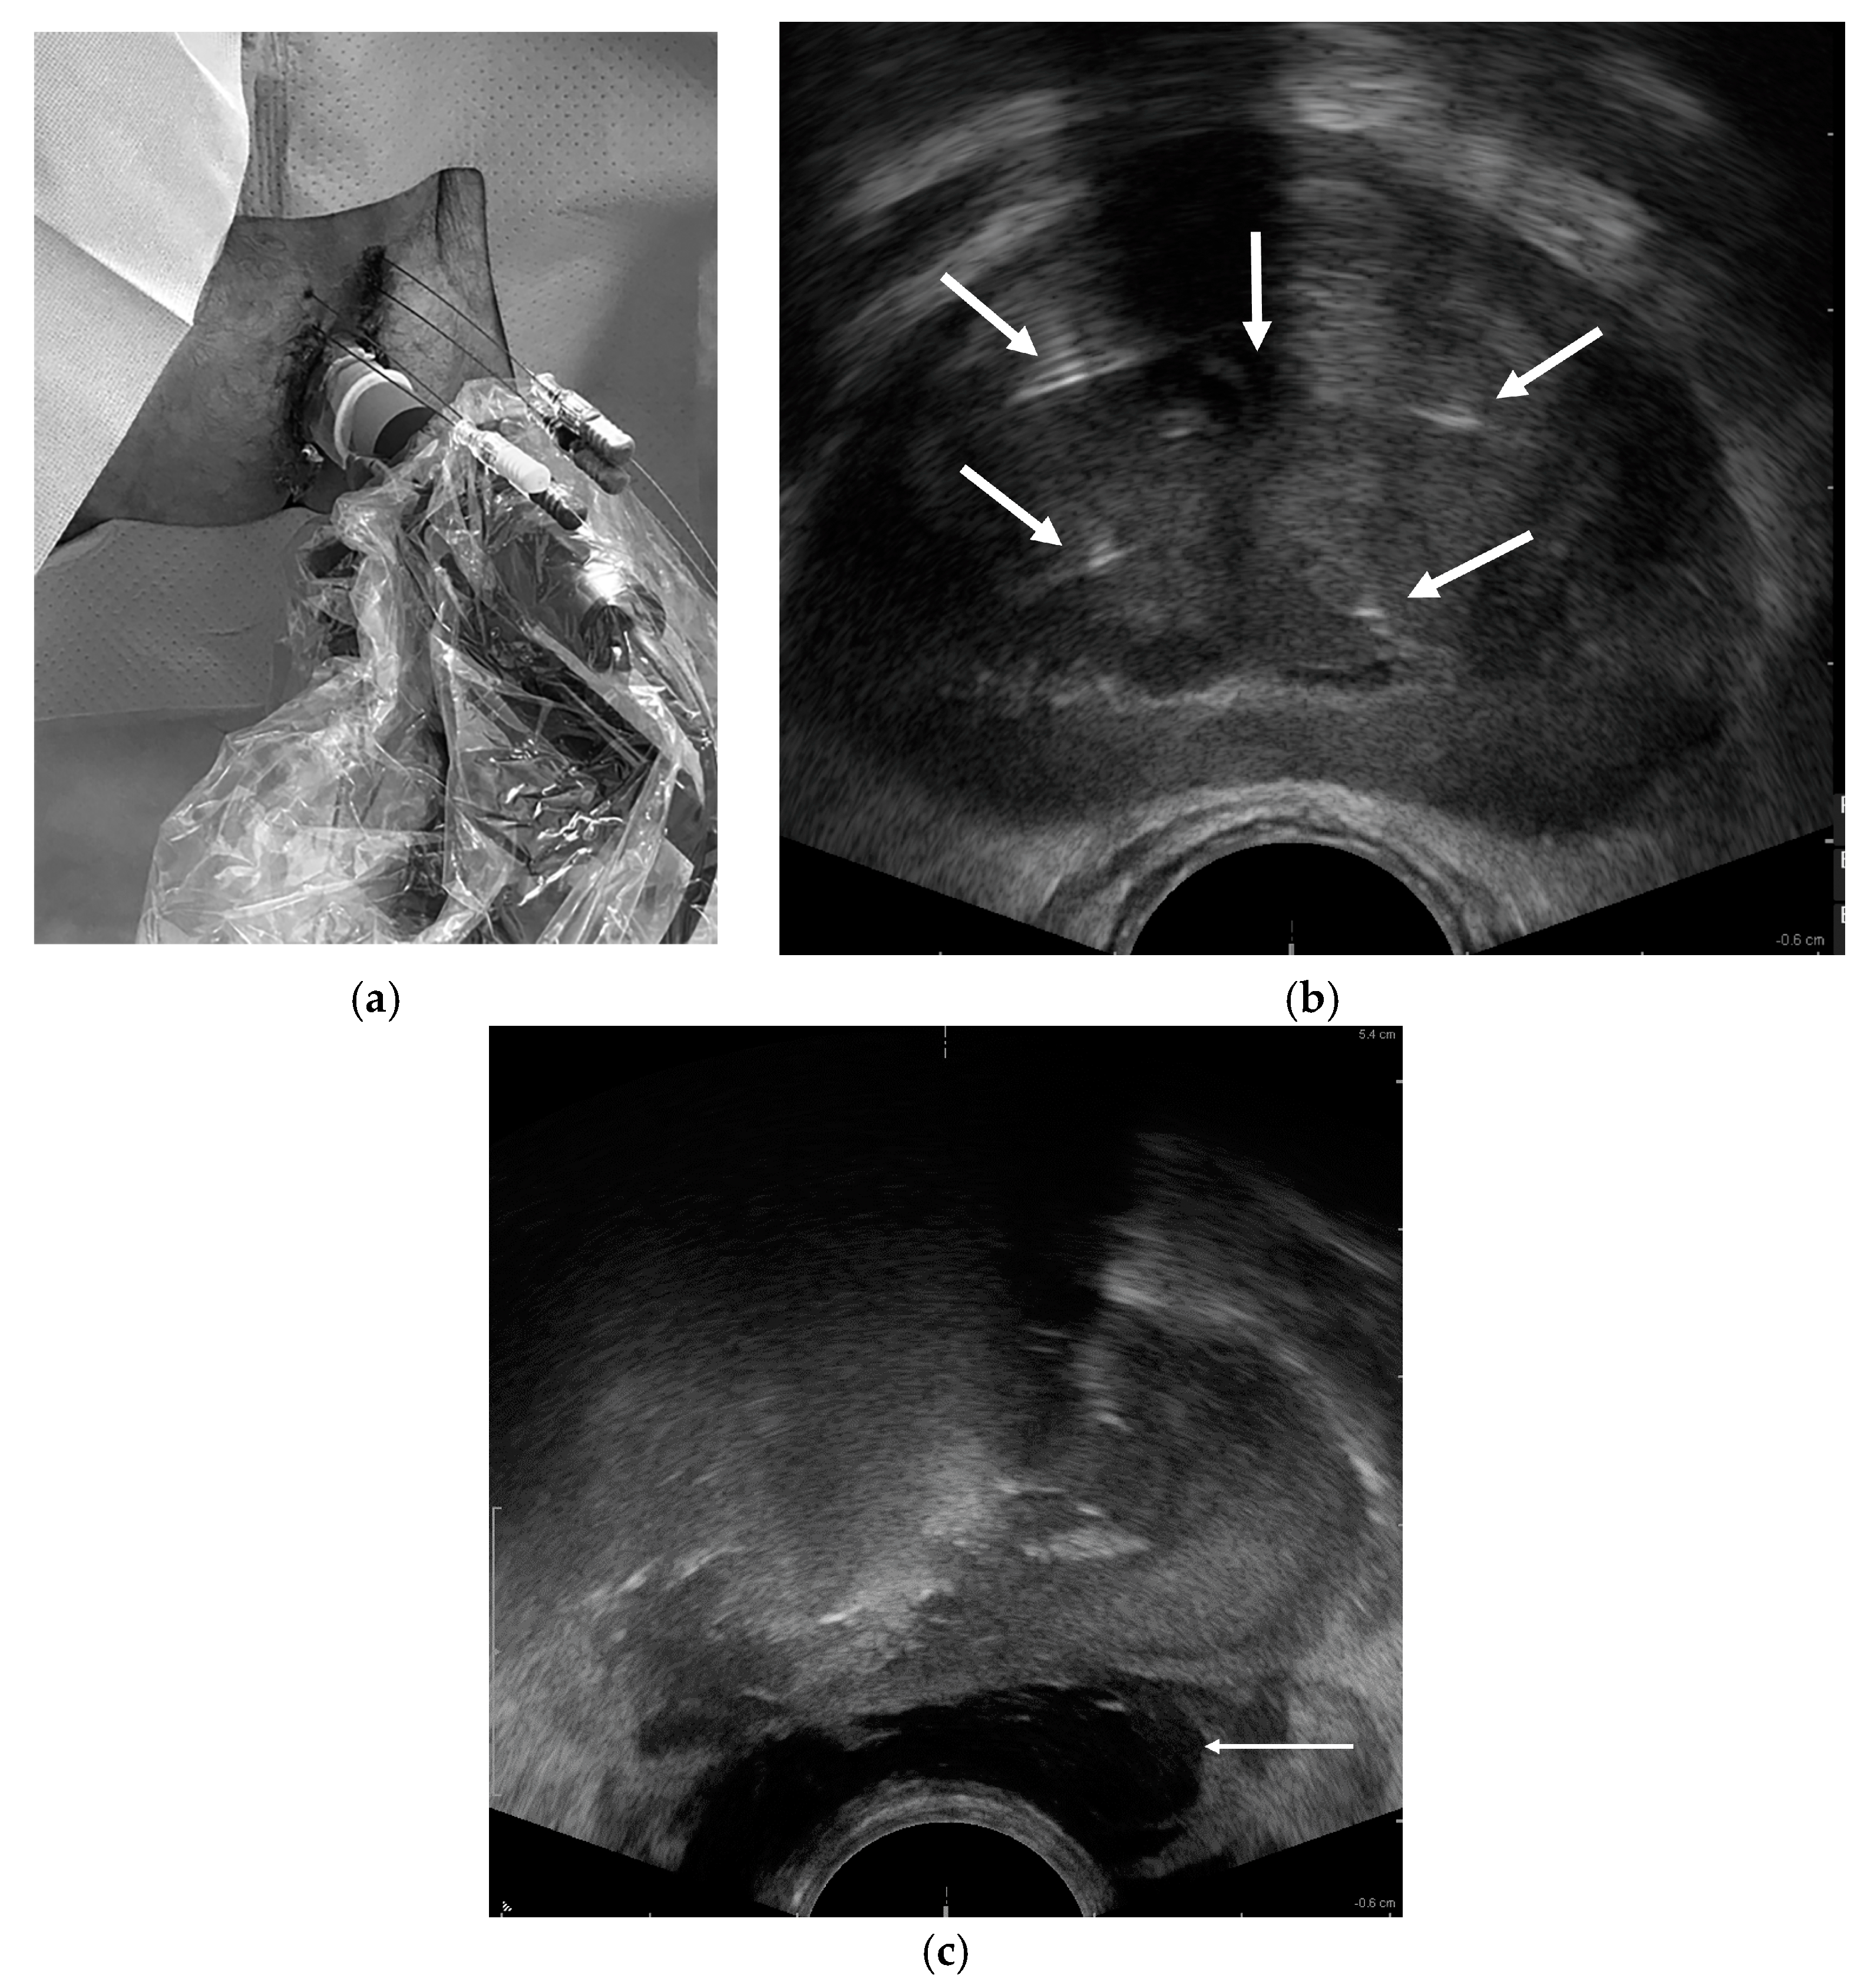

- Manenti, G.; Perretta, T.; Calcagni, A.; Ferrari, D.; Ryan, C.P.; Fraioli, F.; Meucci, R.; Malizia, A.; Iacovelli, V.; Agrò, E.F.; et al. 3-T MRI and clinical validation of ultrasound-guided transperineal laser ablation of benign prostatic hyperplasia. Eur. Radiol. Exp. 2021, 5, 41. [Google Scholar] [CrossRef] [PubMed]

- Laganà, A.; Di Lascio, G.; Di Blasi, A.; Licari, L.C.; Tufano, A.; Flammia, R.S.; De Carolis, A. Ultrasound-guided SoracteLite™ transperineal laser ablation (TPLA) of the prostate for the treatment of symptomatic benign prostatic hyperplasia (BPH): A prospective single-center experience. World J. Urol. 2023, 41, 1157–1162. [Google Scholar] [CrossRef] [PubMed]